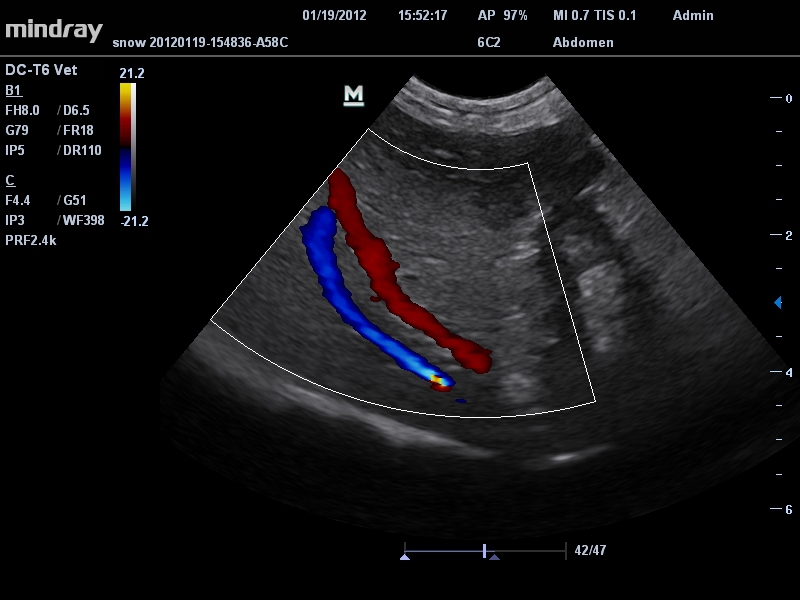

Ветеринария:

Да

• Режимы сканирования: B/M/CFM/PDI/Направленный PDI/PW, HPRF, Тканевая гармоника, М- и цветной М-режим.

• Микроконвексный датчик Mindray 6C2

• Ультраректальный ветеринарный датчик Mindray 6LE5Vs